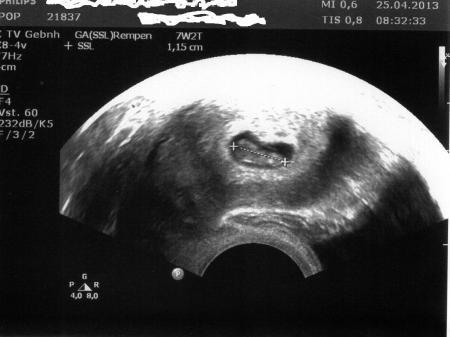

Ich danke euch allen für die Daumen. Meine Tochter war bei einem anderen Arzt, es ist alles ok, das Herzchen schlägt wie wild und es ist ordentlich gewachsen. Woher die Blutung nun genau gekommen ist weiß sie auch nicht, jedenfalls ist jetzt nichts mehr und wir sind alle wieder beruhigt. Zu dem anderen Fa wird sie nimmer gehen. Hab noch ein Bildchen dran gehangen.

Bild zu